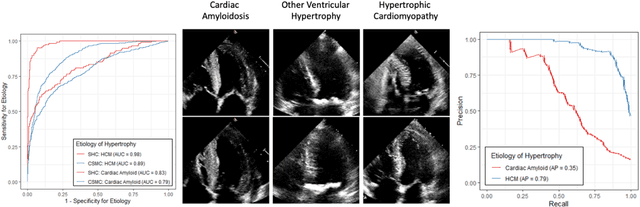

Abstract:Left ventricular hypertrophy (LVH) results from chronic remodeling caused by a broad range of systemic and cardiovascular disease including hypertension, aortic stenosis, hypertrophic cardiomyopathy, and cardiac amyloidosis. Early detection and characterization of LVH can significantly impact patient care but is limited by under-recognition of hypertrophy, measurement error and variability, and difficulty differentiating etiologies of LVH. To overcome this challenge, we present EchoNet-LVH - a deep learning workflow that automatically quantifies ventricular hypertrophy with precision equal to human experts and predicts etiology of LVH. Trained on 28,201 echocardiogram videos, our model accurately measures intraventricular wall thickness (mean absolute error [MAE] 1.4mm, 95% CI 1.2-1.5mm), left ventricular diameter (MAE 2.4mm, 95% CI 2.2-2.6mm), and posterior wall thickness (MAE 1.2mm, 95% CI 1.1-1.3mm) and classifies cardiac amyloidosis (area under the curve of 0.83) and hypertrophic cardiomyopathy (AUC 0.98) from other etiologies of LVH. In external datasets from independent domestic and international healthcare systems, EchoNet-LVH accurately quantified ventricular parameters (R2 of 0.96 and 0.90 respectively) and detected cardiac amyloidosis (AUC 0.79) and hypertrophic cardiomyopathy (AUC 0.89) on the domestic external validation site. Leveraging measurements across multiple heart beats, our model can more accurately identify subtle changes in LV geometry and its causal etiologies. Compared to human experts, EchoNet-LVH is fully automated, allowing for reproducible, precise measurements, and lays the foundation for precision diagnosis of cardiac hypertrophy. As a resource to promote further innovation, we also make publicly available a large dataset of 23,212 annotated echocardiogram videos.